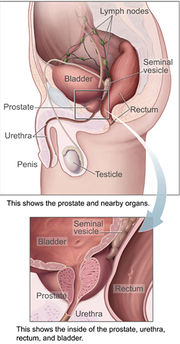

| 1. 6. 2011, 07:25 | Prostata.jpg (soubor) |  | 96 kB | Webmaster | (Zdroj: http://en.wikipedia.org/wiki/File:Prostatelead.jpg) | 1 |